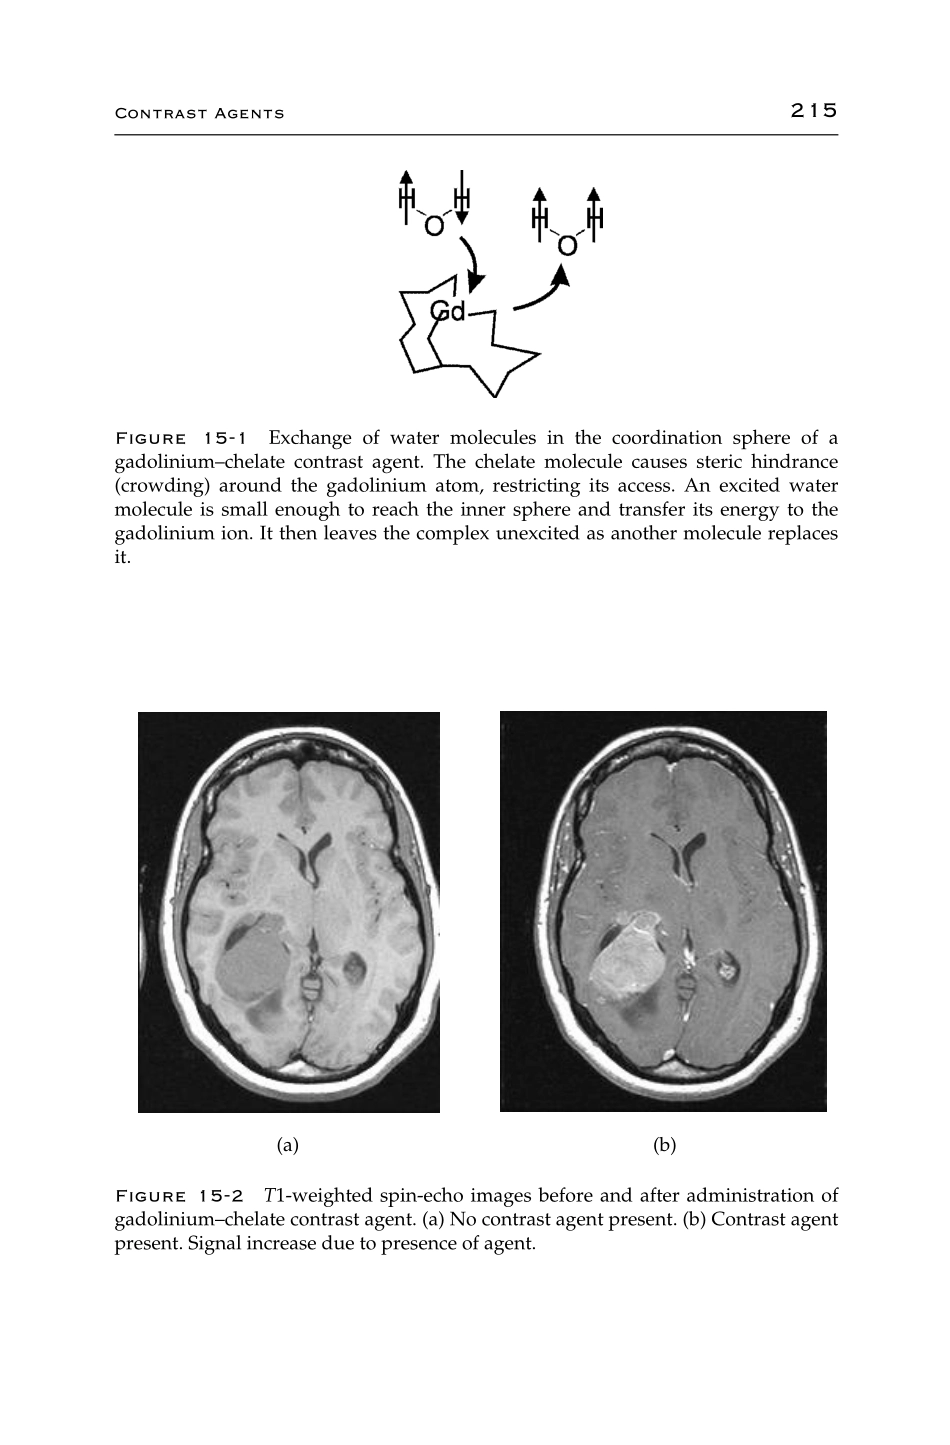

CHAPTER15ContrastAgentsOneofthestrengthsofMRIisthesignificantamountofintrinsiccontrastbetweentissuesthatitproduces.Thiscontrastisbasedupondifferencesinsignalintensitybetweenadjacentpixelsintheimage...